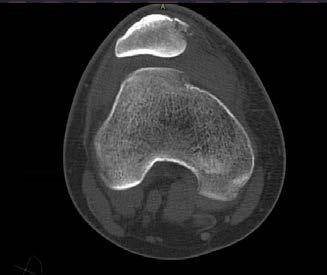

sá sem er mikilvægastur fyrir stöðugleika hnéskeljarinnar. Hnéskelin snertir trissuna fyrst við 20 til 30° beygju um hnéð og við frekari beygju helst hnéskelin stöðug vegna lögunar trissunnar (mynd 1)

Mynd 1

Hliðlægt

Miðlægt